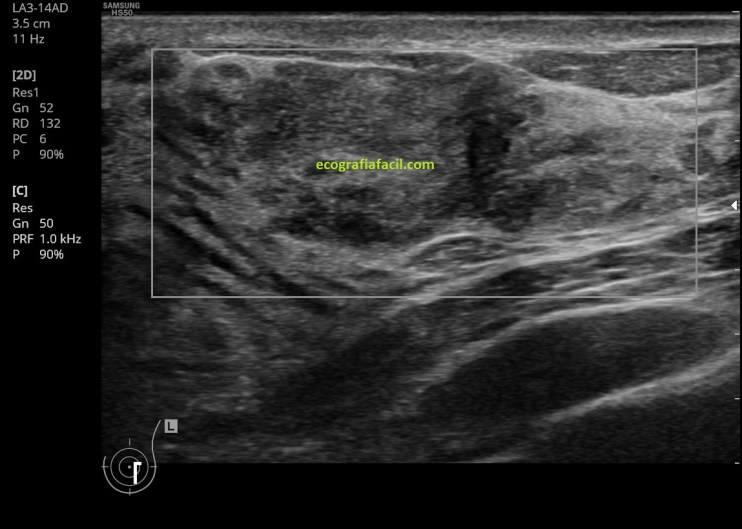

Internamente es, como he dicho, heterogénea (la paleta solo tiene grises, pero en la lesión son muchos y están muy mezclados), como puedes ver en la imagen 2, 3, 5 y 5, la vascularización, imagen 6, en este caso era muy escasa o nula. No hay alteración de los tejidos colindantes de la lesión y ésta, transmite bien.

Finalmente el estudio con el modo color y modo angio para conocer su vascularización.